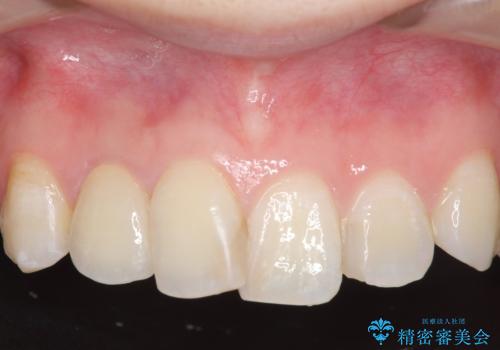

- 右上2番目の歯の被せ物と歯茎の間の継ぎ目が気になるといらっしゃった方の症例です。

再根管治療は希望されなかったため、クラウン除去後、オールセラミッククラウン(スペシャル)による補綴を行いました。

- オールセラミッククラウン(スペシャル)…¥130,000、仮歯…¥10,000、ファイバーコア…¥20,000費用は治療当時の料金となります

前歯の補綴ではオールセラミッククラウンを希望される患者様が多いですが、オールセラミッククラウンの中でも、エコノミー、スタンダード、スペシャル、エクセレントとランクがあります。

その中でも特に審美性が高いのがスペシャル、エクセレントです。スペシャル、エクセレントは口腔内写真をもとに熟練の技工士が、患者様の口腔内に合わせたオーダーメイドのクラウンを製作致します。